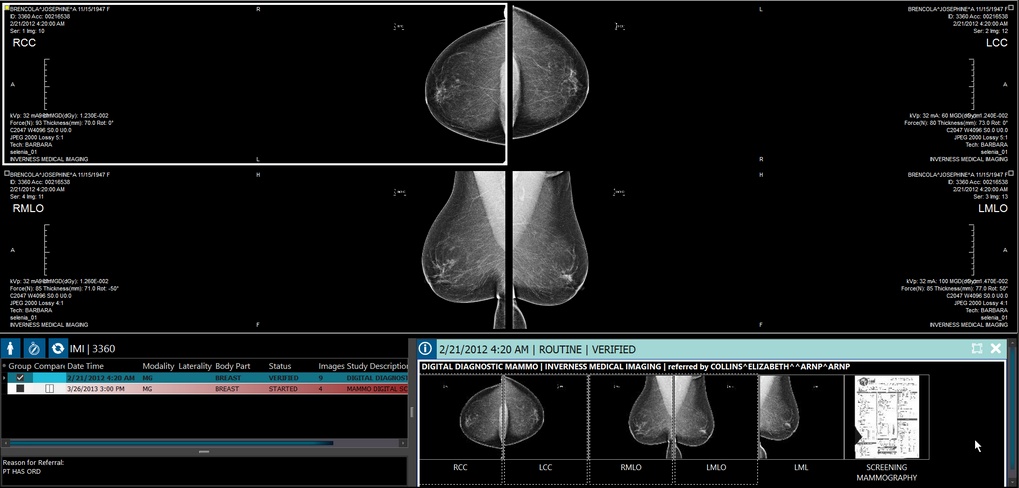

Mammography Thumbnails

Mammography images thumbnail descriptions are now annotated with the view they are located in along with modifier on one line and any information on ImageType3 if there is one existing. They appear as LMLO, RMLO, LCC, RCCID, etc.

MG studies are labeled as LCC, LMLO, RCCID, RMLO, etc.